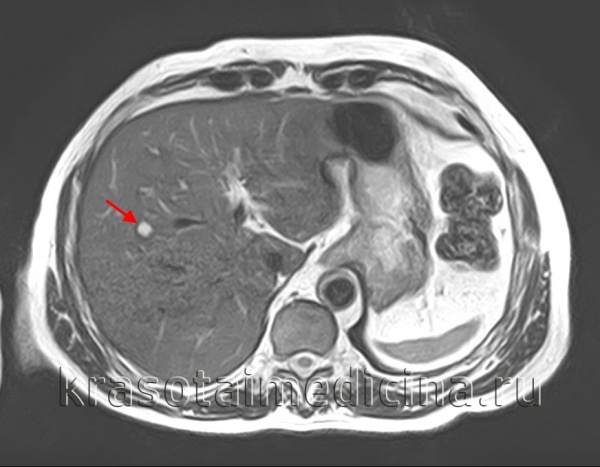

- УЗИ или КТ органов брюшной полости могут помочь определить наличие кисты и её размеры.